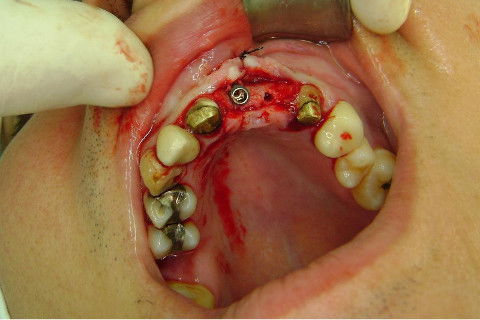

Cirurgia realizada hoje de manhã...No planejamento percebi medindo espessura do rebordo com especímetro que as medidas não estavam muito boas, ou o ideal, em torno de 4,5 a 5 mm ate´o terço médio do rebordo e melhorava no final, com 6 a 7 mm. Optei então por uma pequena expansão usando os expansores rosqueáveis. Aconteceu uma pequena fenestração na hora da fixação dos implantes, especialmente na região do 22 que fraturou o início da tábua óssea, mas não me preocupei porque não foi mais do que 2 mm de fratura em direção apical, o implante ficou infraósseo e com boa estabilidade (60 N no 21 e 40 N no 22). Esta fratura tb não deixou osso completamente solto, foi do tipo galho verde, deixei em posição e suturei normalmente. Só não fiz e nem estava planejado carga imediata mesmo, mais pelo motivo da oclusão inadequada do caso.